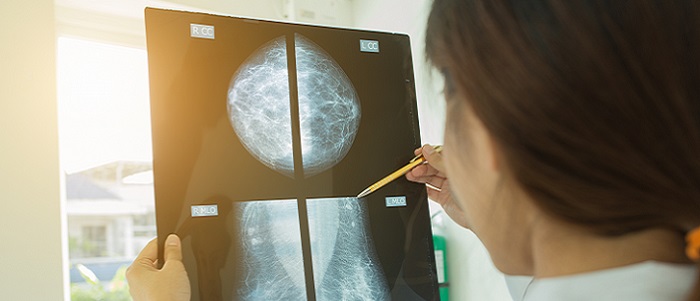

New discovery could halt secondary breast cancer growth